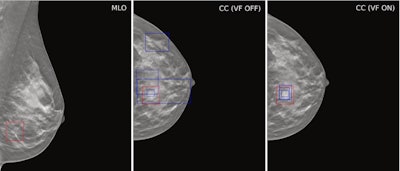

Example case demonstrating improved accuracy in lesion location with ViewFinder (VF) on versus VF off. The mediolateral oblique (MLO) view shows the source reference-standard annotation (red), while the craniocaudal (CC) images show individual radiologist annotations (blue) for both, ViewFinder ON and OFF, and the reference standard annotation

(in red). Courtesy of Stephen Morrell, PhD, et al and EJR. (Note: For interpretation of the references to color in this figure legend, the reader is referred to the original version of this article.)